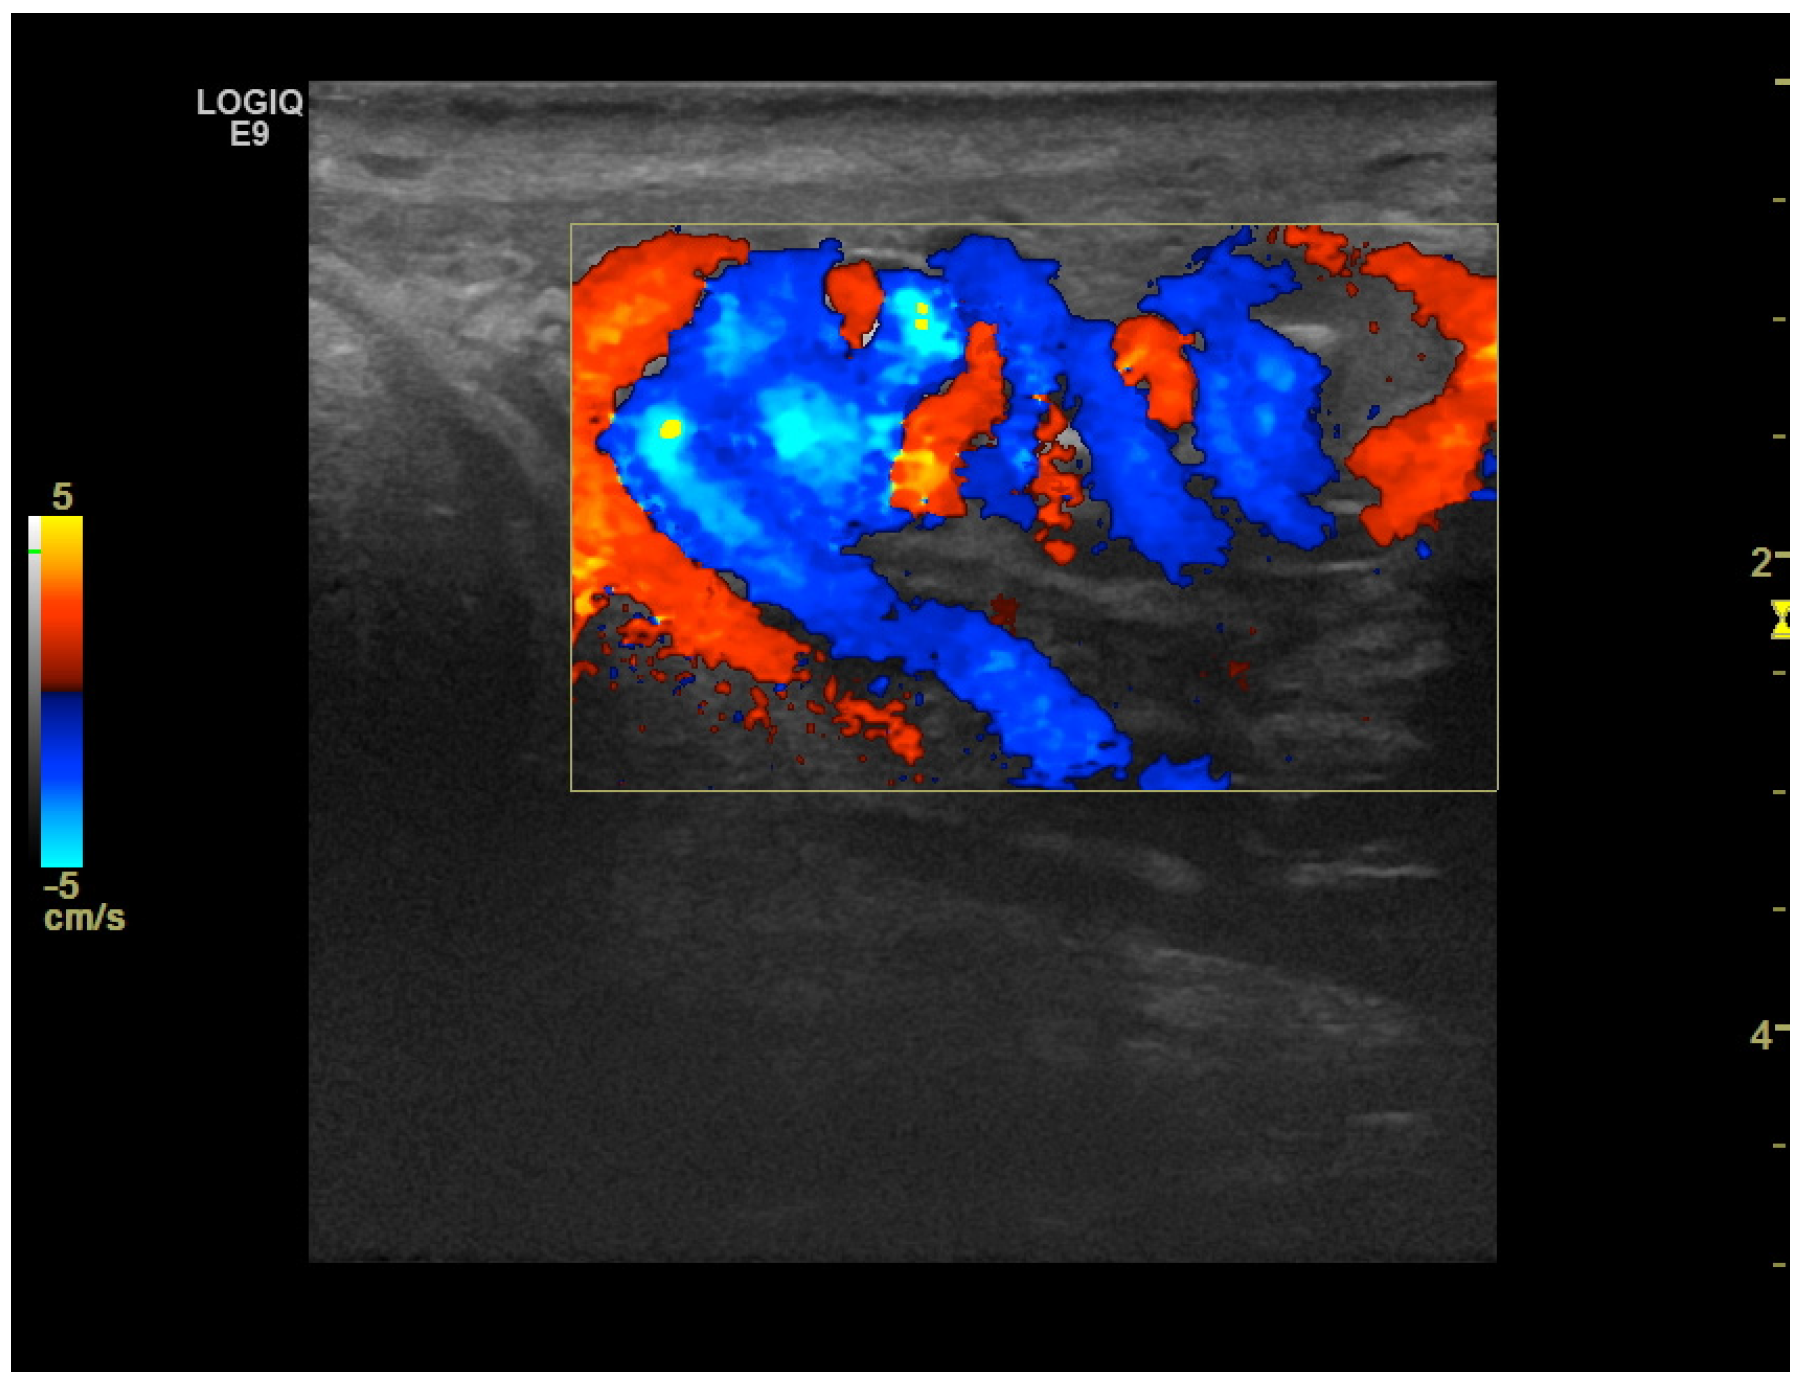

CD was employed to determine the vascularization of the mass. To maximize sensitivity to slow flow velocities, CD was performed using the highest signal gain setting possible (without the appearance of background noise) and low pulse repetition frequencies, allowing for the demonstration of peripheral lesional vascularity (Figure 3 and Video S2). A grade 4 varicocele was also diagnosed via Doppler sonography: dilatation of the veins of the pampiniform plexus around the testis to over 2.5–3 mm and backward flow toward the testes during Valsalva’s maneuver were observed (Figure 4).

Figure 3. Color Doppler image obtained using 8 MHz frequency transducer shows mainly peripheral Doppler signals within the mass.